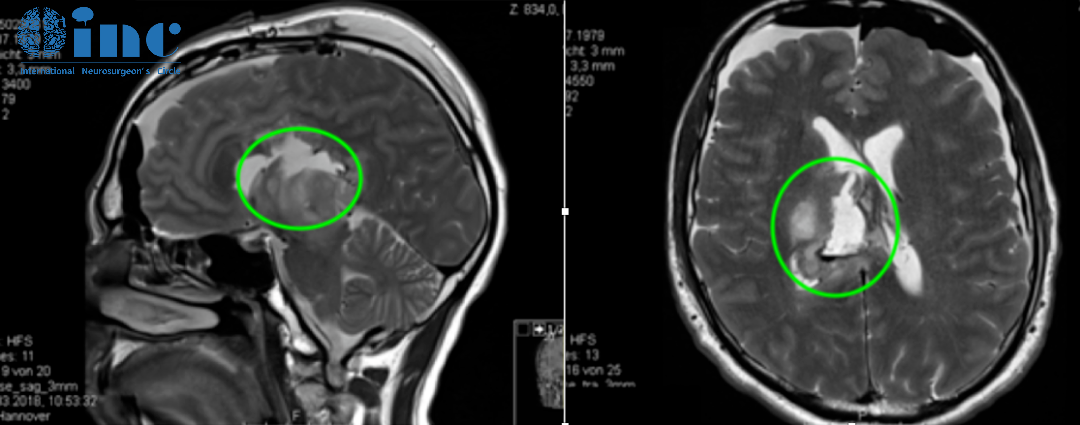

3岁男孩巨大丘脑胶质瘤,手术+化疗效果良好

患者情况:3岁患儿因呕吐和巨脑畸形就医。CT及MRI显示右侧丘脑病变伴钙化及后三脑室梗阻,引起脑积水。

主诊医生:INC世界神经外科顾问团成员、加拿大多伦多大学儿童医院(SickKids)James T.Rutka教授团队。

在8岁、11岁和13岁时,James T.Rutka教授成功地利用第三脑室内窥镜切开术治疗脑积水,且影像显示肿瘤增大和多发肿瘤囊肿(箭头状),并逐渐出现左上肢震颤。

患儿在13岁时进行了神经导航和超声引导下的活检,证实为脑瘤为WHO I级,毛细胞星形细胞瘤。肿瘤囊肿持续扩大,患儿发展为急性偏瘫。

术后MRI显示囊性占位接触,脑室慢慢恢复正常。四个月后,由于患儿的偏瘫没有改善,Rutka教授为其行经胼胝体半球间入路及肿瘤次全切除术。这一次手术后,患儿偏瘫改善,生长和智力发育正常,近期随访显示脑瘤未复发。免疫组化检测RAFV600E突变免疫无阳性,H3K27M阴性。

术后MR显示肿瘤次全切除,无复发